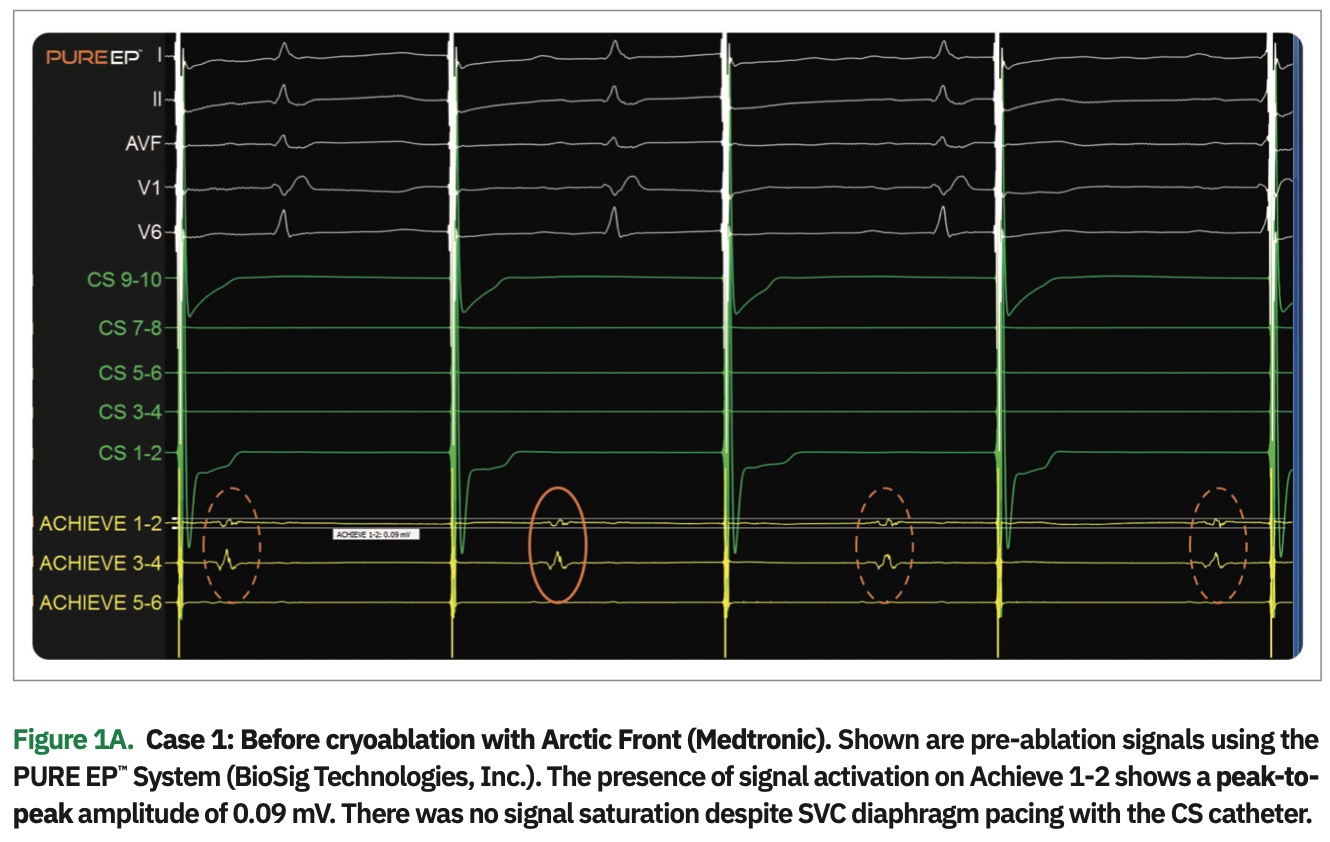

My first encounter with the PURE EP™ System honestly overwhelmed me. While we already have multiple screens of data to look at during the procedure, here was yet another screen of data that I had to view and process. But, as I did more procedures, I realized I became more reliant on the signals provided by the PURE EP™ System. The quality of the signals is excellent. The electrograms provided by the system are superior to those available from all other systems. There were situations where detailed electrograms were available on PURE EP™ and lacking on other systems. The PURE EP™ signals affect my decisions about PVC origin and optimal site of RF ablation. I noted similar findings during ablation of scar-mediated macro-reentry in the left atrium in patients that had undergone more than one prior ablation for atrial fibrillation. Now, I find the PURE EP™ signals indispensable. We have used the PURE EP™ System in different clinical scenarios using both cryo and RF, and found the signals to be equally beneficial, as seen in the figures here.